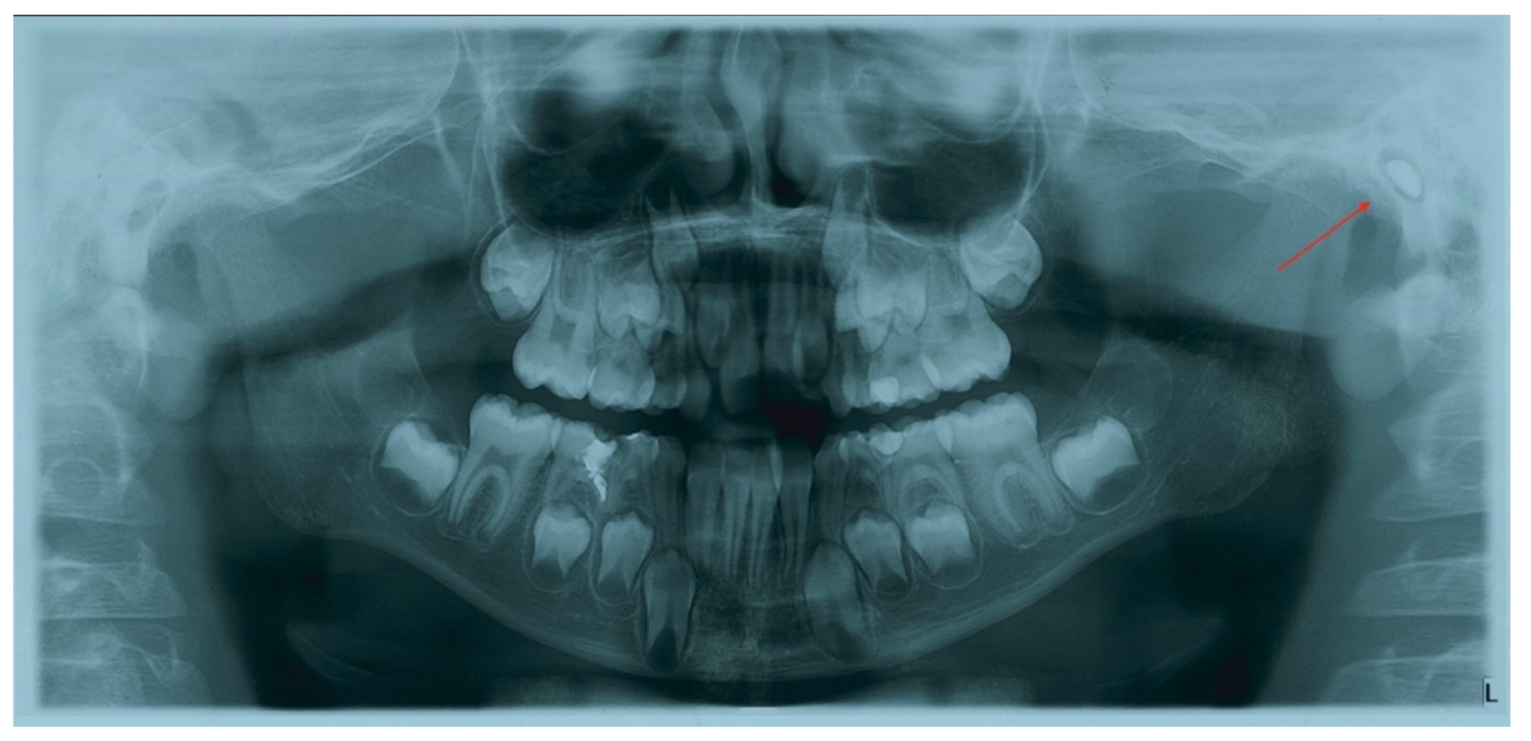

2. Case Report